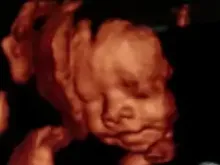

Para a CIDH, uma ultrassonografia é um crime maior que o aborto